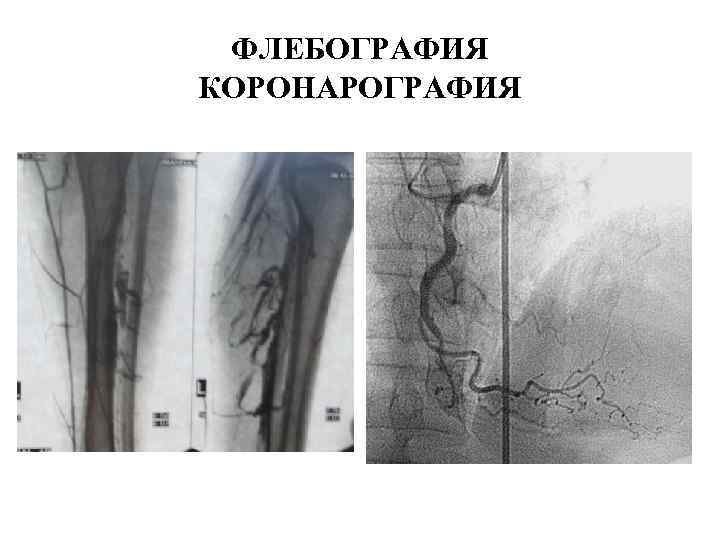

ФЛЕБОГРАФИЯ КОРОНАРОГРАФИЯ

ФЛЕБОГРАФИЯ КОРОНАРОГРАФИЯ